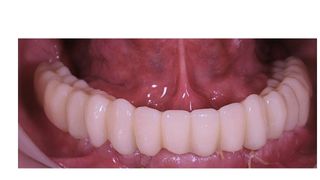

ПРОТЕЗУВАННЯ – ВСТАНОВЛЕННЯ КОРОНОК

Після завершення процесу приживлення імплантатів (остеоінтеграції), яка може займати від 2-4 місяців.

🟢 Поверніть собі усмішку без болю та очікувань.

Ми знаємо як важливо жити повноцінно, не чікаючи пів року на кожен етап. Саме тому звертаються до нас: швидко, естетично, комфортно, доступно.